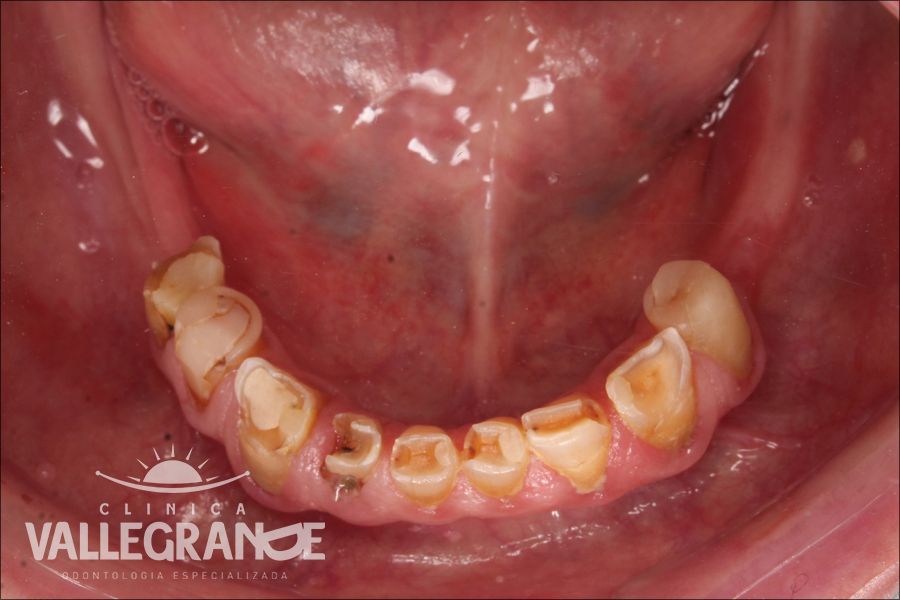

Caso de Rehabilitación Oral planificado en base a prótesis fijas unitarias(coronas) prótesis fijas plurales (puentes) y en base a coronas sobre implantes dentales . Se realizó planificación digital y se rehabilito la totalidad de la boca . No se realizó la extracción de ningún diente.